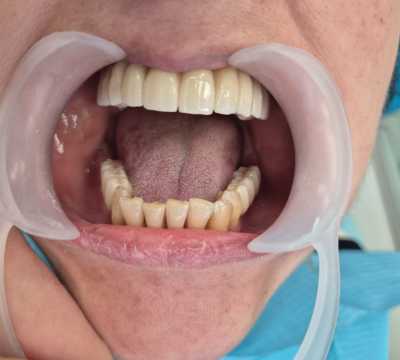

Pacient in varsta de 67 de ani, cunoscut cu boala parodontala severa cu mobilitate avansata a tuturor dintilor, care se prezinta in cadrul clinicii noastre atat din motive functionale, cat si estetice.

Acesta a optat pentru extractia dintilor afectati si protezarea fixa cu ajutorul implanturilor dentare, pacientul dorind respectarea formei si a culorii danturii proprii. Avand in vedere pierderea osoasa importanta, cauzata de patologia pacientului, acesta a necesitat in vederea reabilitarii, atat de sinus lift extern, cat si de aditie osoasa cu os artificial si membrana de colagen.

S-au inserat 10 implanturi dentare la nivel maxilar si 7 la nivel mandibular, pe baza carora s-au realizat protezari fixe metalo-cermice mandibular si ceramica pe zirconiu la nivel maxilar.